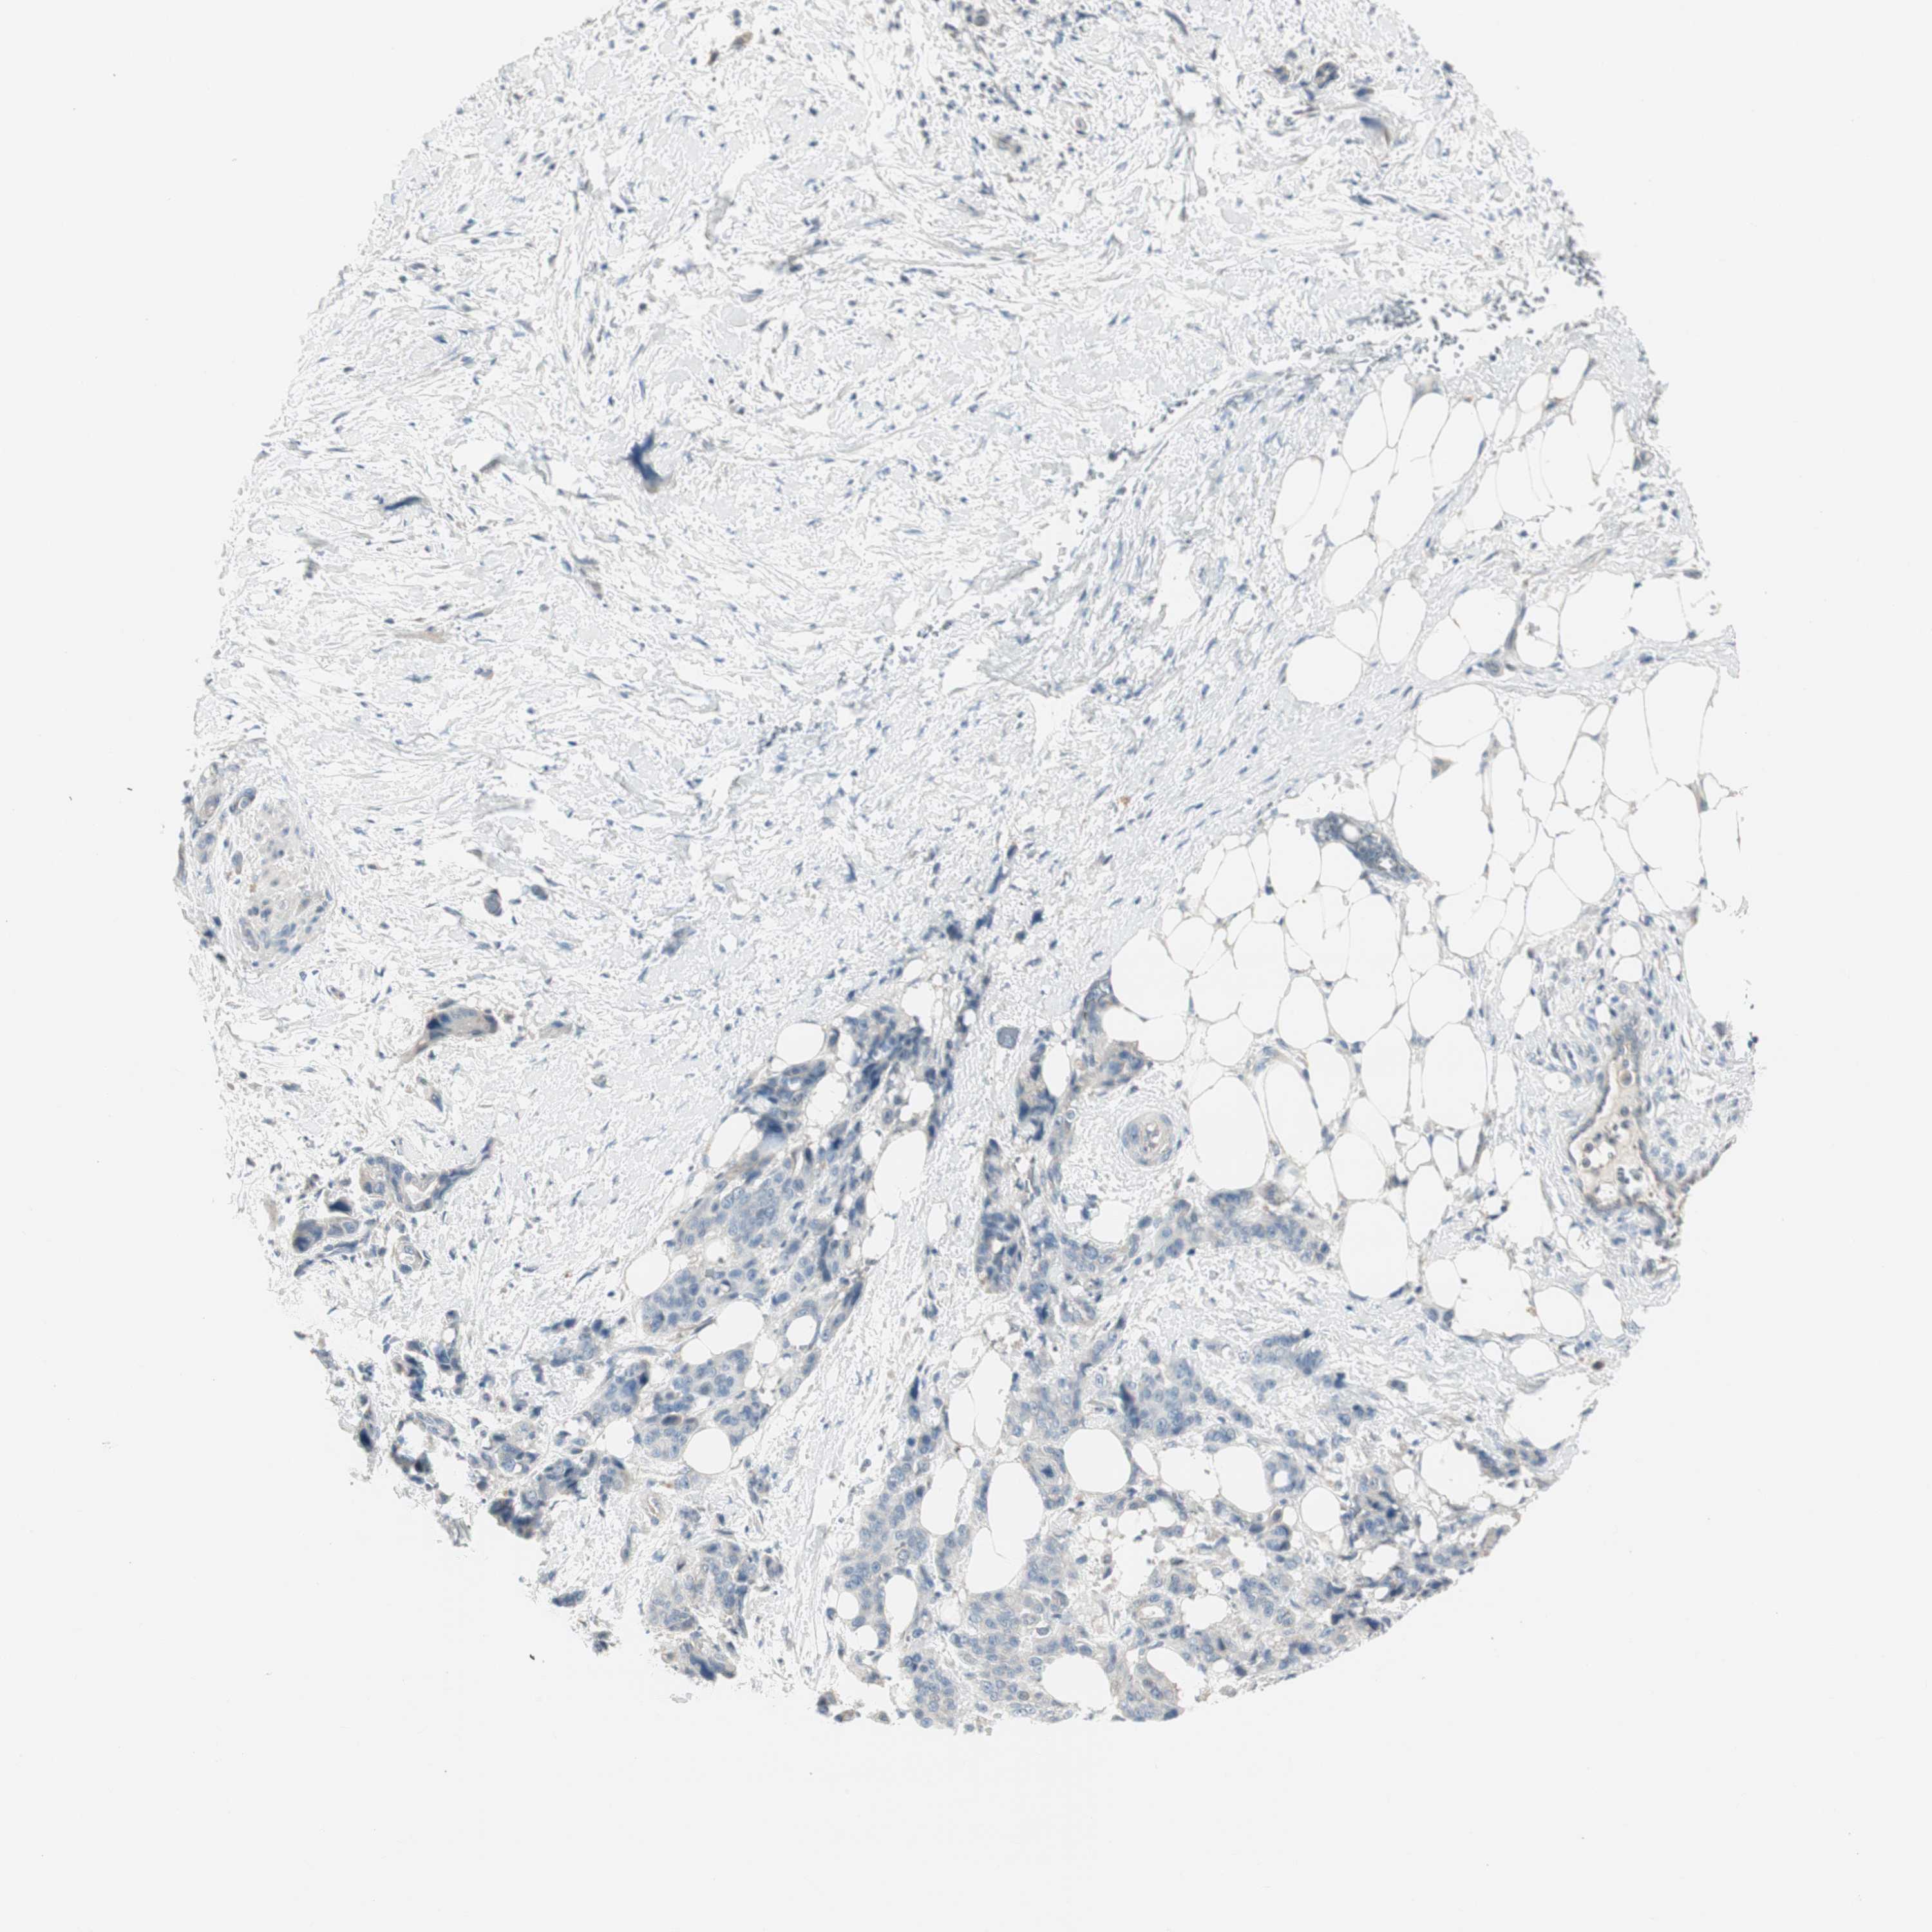

PANCREATIC CANCER - Protein expressioni

A mouse-over function shows sample information and annotation data. Click on an image to view it in a full screen mode. Samples can be filtered based on level of antibody staining by selecting one or several of the following categories: high, medium, low and not detected. The assay and annotation is described here.

Note that samples used for immunohistochemistry by the Human Protein Atlas do not correspond to samples in the TCGA dataset.

Antibody stainingi

Antibody staining in the annotated cell types in the current human tissue is reported as not detected, low, medium, or high, based on conventional immunohistochemistry profiling in selected tissues. This score is based on the combination of the staining intensity and fraction of stained cells.

Each image is clickable and will lead to virtual microscopy that enables deeper exploration of all samples and also displays staining intensity scores, fraction scores and subcellular localization as well as patient and tissue information for each sample.

Antibody HPA008055

Staining

High

Medium

Low

Not detected

Intensity

Strong

Moderate

Weak

Negative

Quantity

>75%

75%-25%

<25%

None

Location

Nuclear

Cytoplasmic/membranous

Cytoplasmic/membranous,nuclear

Adenocarcinoma, NOS

Adenocarcinoma, metastatic, NOS